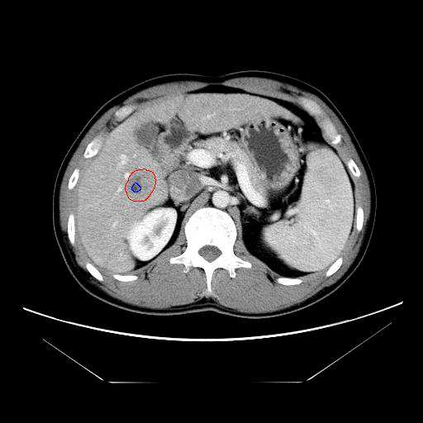

Multi-phase computed tomography (CT) images provide crucial complementary information for accurate liver tumor segmentation (LiTS). State-of-the-art multi-phase LiTS methods usually fused cross-phase features through phase-weighted summation or channel-attention based concatenation. However, these methods ignored the spatial (pixel-wise) relationships between different phases, hence leading to insufficient feature integration. In addition, the performance of existing methods remains subject to the uncertainty in segmentation, which is particularly acute in tumor boundary regions. In this work, we propose a novel LiTS method to adequately aggregate multi-phase information and refine uncertain region segmentation. To this end, we introduce a spatial aggregation module (SAM), which encourages per-pixel interactions between different phases, to make full use of cross-phase information. Moreover, we devise an uncertain region inpainting module (URIM) to refine uncertain pixels using neighboring discriminative features. Experiments on an in-house multi-phase CT dataset of focal liver lesions (MPCT-FLLs) demonstrate that our method achieves promising liver tumor segmentation and outperforms state-of-the-arts.